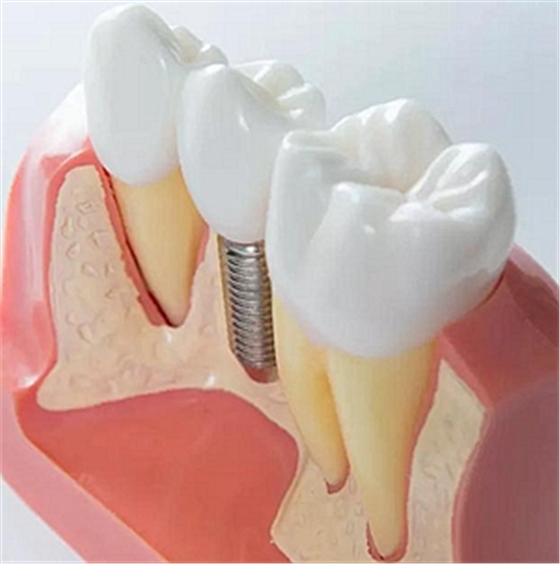

上頜后牙缺失患者常由于先天性上頜竇底位置過低、牙槽骨嚴(yán)重吸收、萎縮等原因, 使骨量高度不足。直接植入種植體易穿入上頜竇引起感染等并發(fā)癥, 導(dǎo)致種植失敗。上頜竇底提升技術(shù)(Maxillary Sinus FloorLifting)是采用外科手術(shù)方法將上

頜竇黏膜從竇底剝離后抬高,在竇底黏膜與竇底骨之間植入骨移植材料,有效增加骨的高度,在此基礎(chǔ)上植入種植體,使種植體獲得足夠的高度及初期穩(wěn)定性。

目前骨移植材料多使用生物相容性較好的人工骨粉。根據(jù)手術(shù)方法的不同,上頜竇底提升術(shù)主要分為兩種:上頜竇內(nèi)提升和上頜竇外提升。